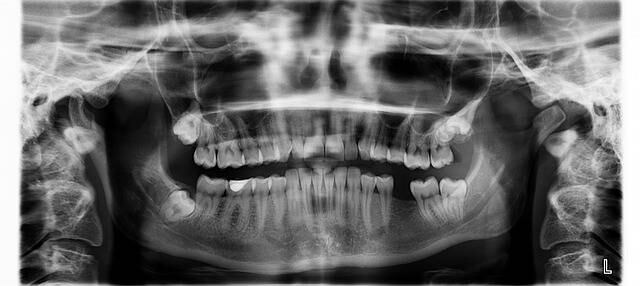

Y es que según informa el New India Express, los doctores ordenaron realizarle al niño una radiografía y una tomografía computarizada para encontrar el problema, y fue allí cuando notaron algo increíble: el paciente tenía más de 500 dientes en su boca.

Exactamente, el niño tenía 526 dientes.

"La radiografía y la tomografía computarizada mostraron múltiples dientes rudimentarios en un tejido similar a una bolsa".